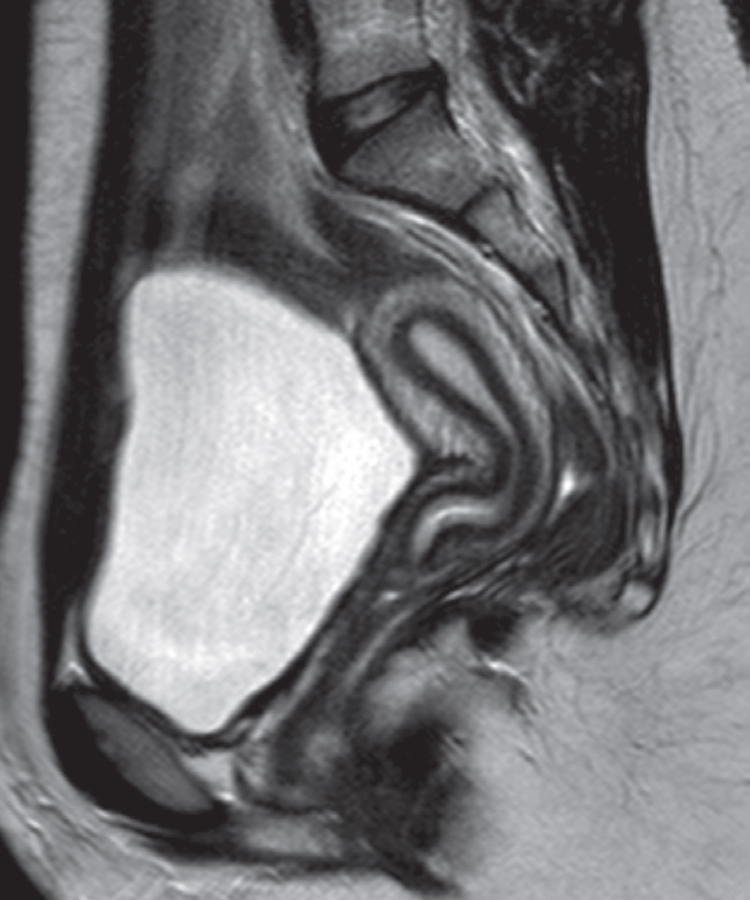

Normal uterus on sagittal T2-weighted MRI. The endometrium returns a high signal intensity. The cervix is in continuity with the lower uterine body.